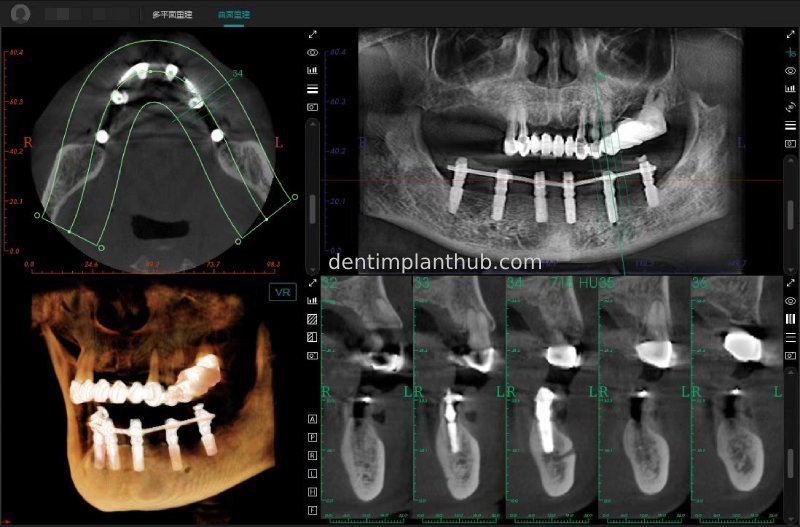

Maxillary condition as shown by CBCT on 13/5/24

16

14

12

22

24

26

Details of implant sites, protocols, implant types, composite abutments, 13.5.24

16, implant model 4810, requires an internal elevation of the maxillary sinus floor and an RC series straight composite abutment;

14, implant model 4812, requires an RC series 15° composite abutment;

12, implant model 4112, requires an RC series 30° composite abutment;

22, implant model 4112, requires an RC series 30° composite abutment;

24, implant model 4812, requiring an RC Series 15° composite abutment;

26, implant model 4810, requiring an internal maxillary sinus floor lift, requiring an RC Series straight composite abutment;